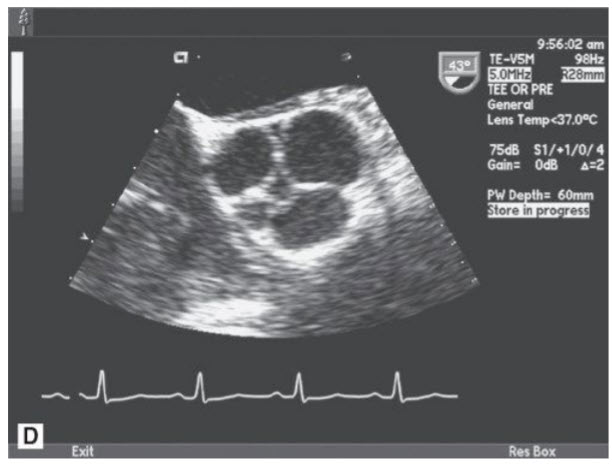

The following TEE image (Fig. below)

Bicuspid AV with fusion of the RCC and LCC. The 2D TEE midesophageal view (see Fig. in question) demonstrates a bicuspid AV in short axis. To determine cusp anatomy one must view the AV in systole. If one looks for a “Mercedes Benz” image of the valve in short axis during diastole (Fig. below A), one may mistake a bicuspid valve for a tricuspid valve, not realizing that one of the arms in the Mercedes Benz sign is actually a calcified raphe between two fixed cusps. Thus, it is important to look at the valve in systole to determine the true cusp anatomy. The most common form of bicuspid AV is fusion of the RCC and LCC. Bicuspid AVs are also associated with a dilated aorta with an aortopathy involving cystic medial necrosis. Another form of bicuspid AV is fusion of the RCC and NCC (Fig. below B). There are other congenitally abnormal AVs, including unicuspid valves (Fig. below C) and quadricuspid valves (Fig. below D). The unicuspid and quadricuspid valves are much less common than bicuspid valves.